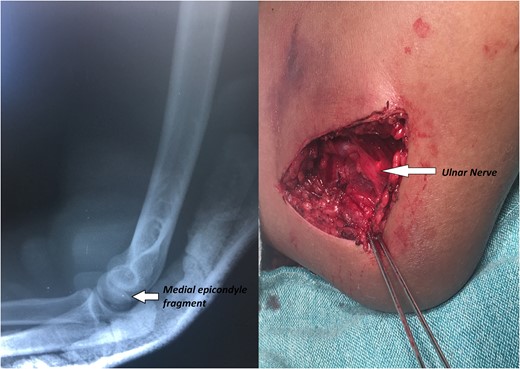

A 14-year-old male patient presented to the emergencies department complaining of intense pain in the left elbow secondary to a fall with an outstretched hand while practicing soccer. He had no significant comorbidities. At physical examination he presented with deformity located on the left elbow, he was unable to passively or actively mobilize it, he reported paresthesias and diminished sensation located on the fifth and fourth digit. X-rays showed a dislocation on the left elbow and an avulsive fracture of the medial epicondyle of the distal humerus (Fig. 1). He was taken to the operating room where a closed manipulation was performed; however the reduction was not achieved due to the interposition of the fractured medial epicondyle. A medial approach to the elbow was performed; intra-operative findings included rupture of the medial capsule and intra-articular interposition of the fragment of the medial epicondyle with a posterolateral dislocation of the elbow, the ulnar nerve showed compressive injuries at the site of the fracture (Fig. 2). Extraction and fixation of the interposed intra-articular fragment was performed followed by elbow reduction and a medial capsule repair, without ulnar nerve transposition (Fig. 3). The patient was left with a posterior splint for a month. After a 3 month follow-up, he has recovered full range of motion of the elbow with recovery of strength and sensation over the distribution of the ulnar nerve.